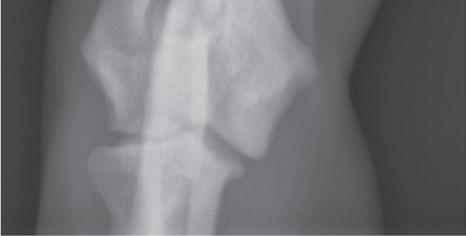

n As already noted, lateromedial or mediolateral images of extremities should be oriented with the proximal aspect of the limb at the top and the cranial or dorsal aspect of the limb heading to the examiner’s left (Figure 1-4). This orientation is correct regardless of whether the left or right limb has been imaged.

n Caudocranial (palmarodorsal or plantarodorsal) or craniocaudal (dorsopalmar or dorsoplantar) images of extremities should be oriented with the proximal aspect at

the top and the distal aspect at the bottom. These can all be considered sagittal-plane radiographs. There is no convention directing whether the medial or lateral side of the extremity should be on the examiner’s left (Figure 1-5). This orientation is correct regardless of whether the left or right limb has been imaged.

Figure 1-4. Correct orientation of lateral views of two extremities. A lateral view of a humerus (A) and a lateral view of a tarsus/pes (B) are shown here. Note the difference in directional terms depending on whether the part being imaged is above or below the tarsocrural or antebrachiocarpal joint.

Figure 1-5. Correct orientation of a sagittal-plane radiograph of an extremity. A caudocranial view of a humerus is shown here. There is no convention regarding whether the lateral side of the limb is placed on the examiner’s right (A) or left (B). However, it is probably more common to orient medial and lateral relative to the patient. As such, a left limb would be oriented as in Figure 1-5A, and a right limb would be oriented as in Figure 1-5B.